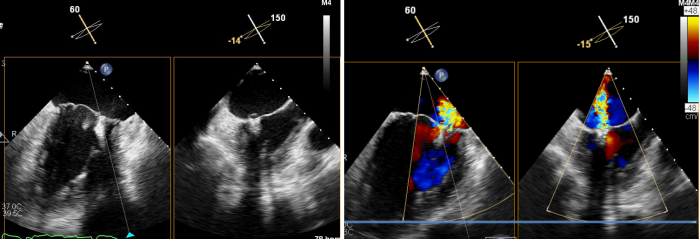

术前,超声科聂红军教授运用全数字化高端心脏彩色多普勒诊断仪,为患者进行食道三维超声综合评估,确定了二尖瓣返流量及返流分区。同时,在手术中实时监测二尖瓣瓣叶返流区与钳夹器的位置是否吻合,术后还可即刻探查二尖瓣返流量减少情况,如果把手术比作开车,那超声科就是手术的导航系统。

术中,蒋路平主任团队在经食道超声引导下通过股静脉穿刺房间隔将二尖瓣钳夹系统送入患者左心房到达二尖瓣口,然后医生全程在经食道超声引导下通过评估二尖瓣返流位置以及返流程度等精准夹合二尖瓣叶,整个过程都是在心脏不停跳的情况下完成。

术前心脏彩超所示:二尖瓣返流

术后心脏彩超所示:二尖瓣无返流

术后,患者二尖瓣返流情况得到了明显改善,其他各项生理指标也均正常,术后第二天即可下床活动,呼吸困难和乏力症状显著缓解,心脏负荷明显减轻。术后心脏彩超结果显示,其左室射血分数上升到62%,生活质量获得极大提升。